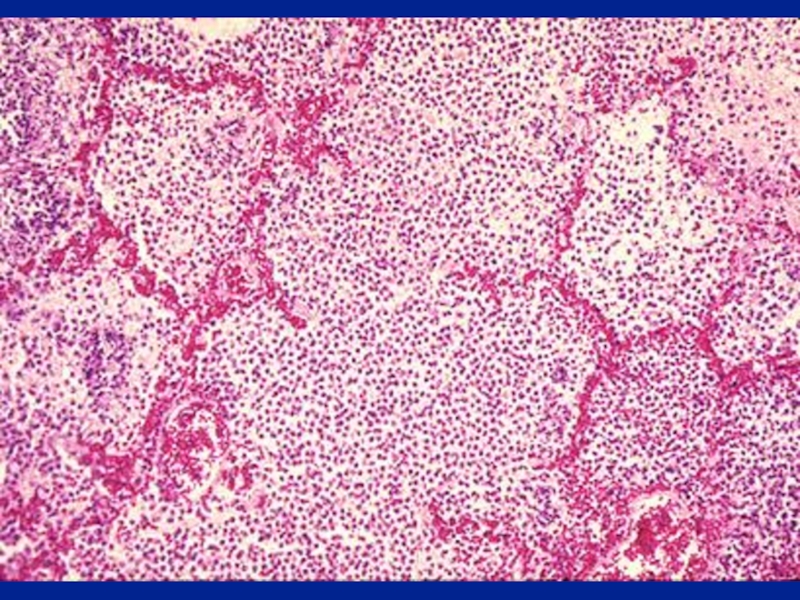

Слайд 48Crackles

Interrupted adventitious sounds are called crackles.

Make a notation about timing,

intensity, effect with respiration, position, coughing and character.

Timing and Intensity

Crackles heard only at the end of inspiration are called fine crackles.

When the surfactant is depleted, the alveoli collapse. Air enters the alveoli at the end of inspiration.

This sound is generated as the alveoli pop open from it's collapsed state.

CracklesInterrupted adventitious sounds are called crackles.Make a notation about timing, intensity, effect with respiration, position, coughing and

Слайд 49Crackles

When the crackles are heard at the end of inspiration

and the beginning of expiration the fluid or secretions are

probably in respiratory bronchioles: medium crackles.

If the crackles are heard throughout it implies the secretions are in bronchi: coarse crackles.

CracklesWhen the crackles are heard at the end of inspiration and the beginning of expiration the fluid